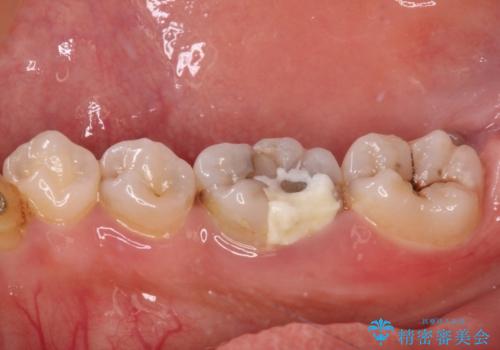

放置した虫歯 根管治療とオールセラミッククラウン

- 奥歯の虫歯を放置してしまい、痛みを感じることがあるとのことで来院された患者様です。

術前の診査では、神経を取り除かなくても済む可能性が示唆されましたが、実際に虫歯除去を進めたところ、レントゲン写真から読み取れる通り、神経組織にまで虫歯が及んでいることが分かりました。

速やかにラバーダム下にて根管治療を行うこととし、その後オールセラミッククラウンにて補綴治療を行うこととしました。